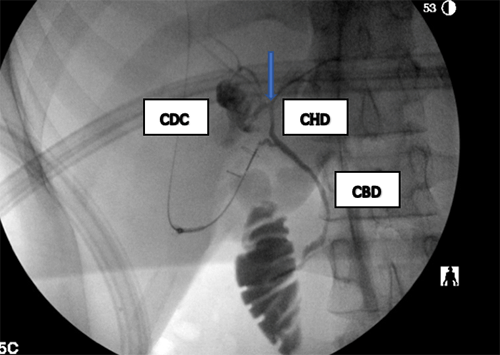

There did not appear to be an obvious choledochal cyst in the field of dissection after mobilization of the gallbladder and hepatoduodenal ligament. An intraoperative cholangiogram was performed, which demonstrated an intrahepatic saccular cyst originating off of the right hepatic duct, with one communicating biliary connection (Figure 3). The cyst appeared to be an intrahepatic type II choledochal cyst. The intrahepatic cyst was dissected away from the liver parenchyma and entered. Sludge and stones were removed, and then the feeding duct off the right hepatic duct was clamped, confirming exclusion of the cyst. The feeding duct was then clipped to exclude the cyst permanently. Complete excision of the cyst was attempted, but the proximity of the right hepatic duct precluded completion of the excision. Mucosectomy was performed except for the portion intimately adhered to the right hepatic duct; the remaining portion of the cyst was fenestrated and fulgurated. A confirmation cholangiogram demonstrated complete exclusion of the cyst and intact biliary tree anatomy (Figure 4).

Figure 4. Completion Cholangiogram Demonstrating Filling of Biliary Tree With Exclusion of Choledochal Cyst. Published with Permission

CBD = common bile duct, CHD = common hepatic duct. Arrow points to right hepatic duct and left hepatic duct bifurcation.